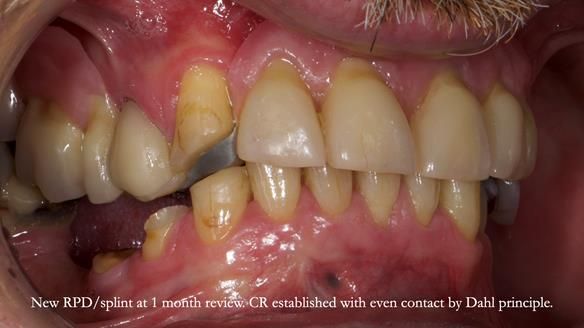

Keith’s case was one of the most challenging and rewarding cases I’ve treated this year. This 64 year old man presented with ill-fitting acrylic partial dentures that lacked stability, retention, and aesthetics. They constantly broke. He had lost the upper front teeth in a road traffic accident in his early 20s. The unopposed teeth had erupted, taking up space. After careful planning, we made a durable, metal-based upper partial denture/splint to address his dental concerns. He loved the outcome.

Keith’s denture incorporated a Duracetal shell clasp on upper right first premolar (Myerson), which are designed to be virtually visible, providing a more aesthetic solution while enhancing patient comfort. The Scandinavian-inspired approach, based in modern removable prosthodontic techniques, ensured the denture was not only durable but also visually pleasing. Additionally, the design was carefully planned to allow for future modifications, ensuring that if Keith loses additional teeth, the denture can be adapted rather than replaced entirely.

I also used the Dahl concept to re-establish the occlusion upon fitting the RPD, which helped to intrude the lower left canine without needing to grind it too much.